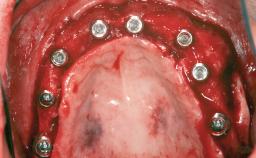

A 20-year-old woman was referred for implant therapy in 2004. Her medical history revealed no significant findings, and neither did she smoke nor take any medications. An extraoral examination revealed no abnormalities of the skin, hair or nails. The intraoral examination revealed only 11 permanent teeth clinically. These were normal in shape, size, and color. In addition, eight retained deciduous teeth (53, 62, 63, 71, 72, 73, 81, 82) were present. No abnormalities were detected during the general examination. The family history revealed that the patient’s father and two sisters were on record with similar conditions. The clinical examination revealed a thick gingival biotype. No recession of the attached gingiva was noted, but the retained deciduous teeth were mobile and unsightly. As a syndrome had not been diagnosed, the case was categorized as non-syndromic oligodontia.